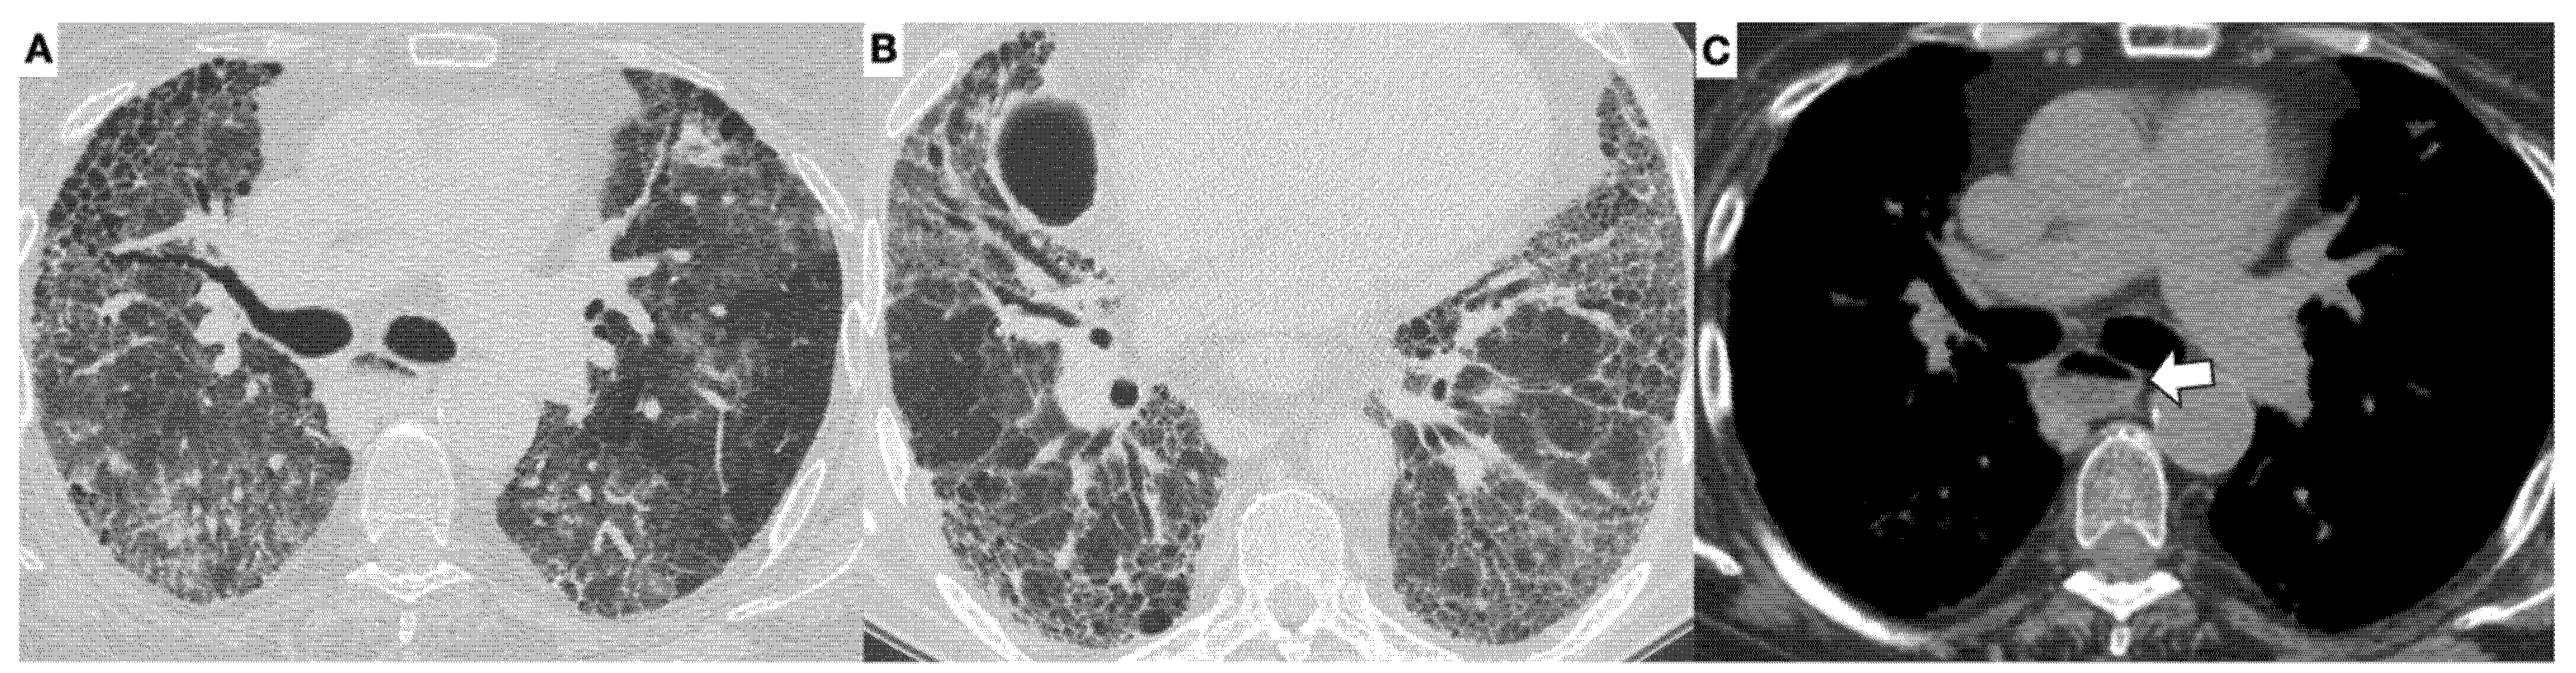

3.1. High-Resolution Computed Tomography in SSc-ILD: Qualitative Evaluation

3.2. High-Resolution Computed Tomography in SSc-ILD: Quantitative Evaluation